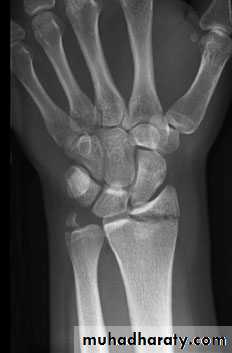

X-RAY

There is a transverse fracture of the radius at the corticocancellous junction, and often the ulnar styloid process is broken off. The radial fragment is impacted into radial and backward tilt. Sometimes there is an intra-articular fracture; sometimes it is severely comminuted.TREATMENT